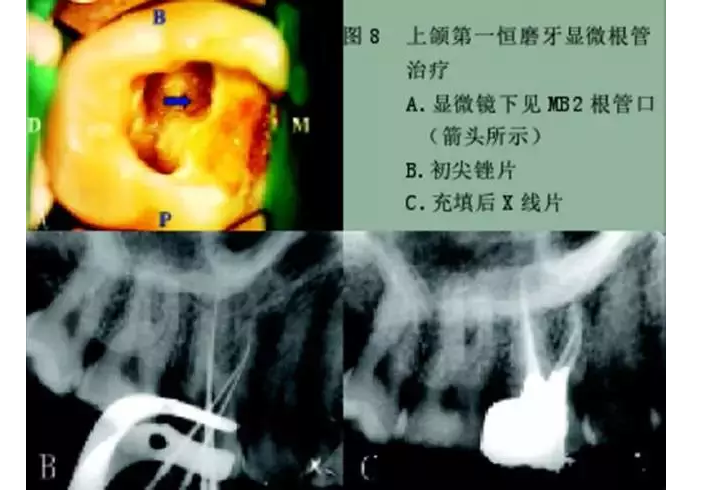

1)尋找遺漏根管

2)根管系統(tǒng)的解剖形態(tài)是極其復雜的。牙髓病學教材中常常提到磨牙有三個根管,前磨牙兩個根管,前牙一個根管。實際上,根管系統(tǒng)并不是如此可預知的,而是常常存在許多解剖變異。根管系統(tǒng)的解剖形態(tài)學研究發(fā)現(xiàn):幾乎50%磨牙中(上頜和下頜)有第四根管存在,30%以上的前磨牙有第三根管,接近25%的前牙有雙根管。

在傳統(tǒng)的根管治療中,開髓后往往只是依靠術(shù)者的視覺和經(jīng)驗去尋找根管,所以常常存在遺漏根管的可能,從而導致根管治療的失敗。研究發(fā)現(xiàn),X線片上顯示根管充填滿意的患牙仍有癥狀的主要原因是有遺漏的根管未治療。

所以對于經(jīng)過完善根管治療后的牙,如果出現(xiàn)持續(xù)疼痛,首先應該考慮可能有遺漏根管的可能。

手術(shù)顯微鏡是用于尋找隱藏或遺漏的根管最重要的工具。因為手術(shù)顯微鏡能夠幫助醫(yī)生觀察到肉眼或普通放大鏡無法分辨的根管口和微小病損。在手術(shù)顯微鏡下,利用高倍數(shù)(16~24倍)的放大作用以及理想的照明條件,仔細檢查患牙的髓室底,許多細微的解剖結(jié)構(gòu)能容易被發(fā)現(xiàn)。

為了光線能充分進入髓腔,髓室頂應完全揭去,開髓口的形態(tài)應根據(jù)具體牙位進行適當修改,使得所有根管口都能夠充分暴露。同時,對髓底進行美藍染色也有助于根管口和微小病損的識別。

對于有些牙根管在根管口下3~5毫米處分叉以及近頰和遠頰根管口非常接近的上頜第二磨牙,手術(shù)顯微鏡更是相當有價值的工具。因為根管的分叉點和獨立的根管口能清楚地在顯微鏡下被觀察到。